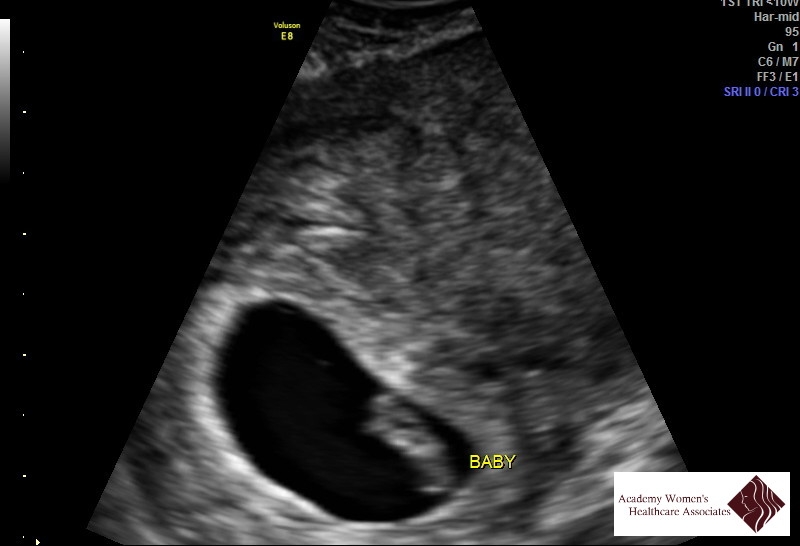

• This is my ultrasound at 8 weeks and 3days 165bpm and 1.9cm(which i hear is big?)